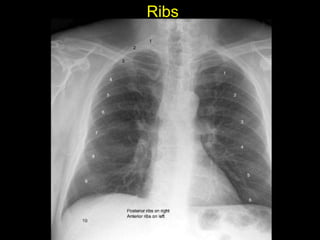

The document discusses the anatomy of the chest x-ray and CT scan by describing the lobes of the lungs and their locations. It also mentions the heart, mediastinum, hilum, and ribs. Several axial, coronal, and sagittal CT images are included with labels pointing out structures like the trachea, bronchi, lobes of the lungs, and fissures. In summary, the document provides an overview of lung and chest anatomy as seen on x-rays and CT scans through text descriptions and labeled medical images.